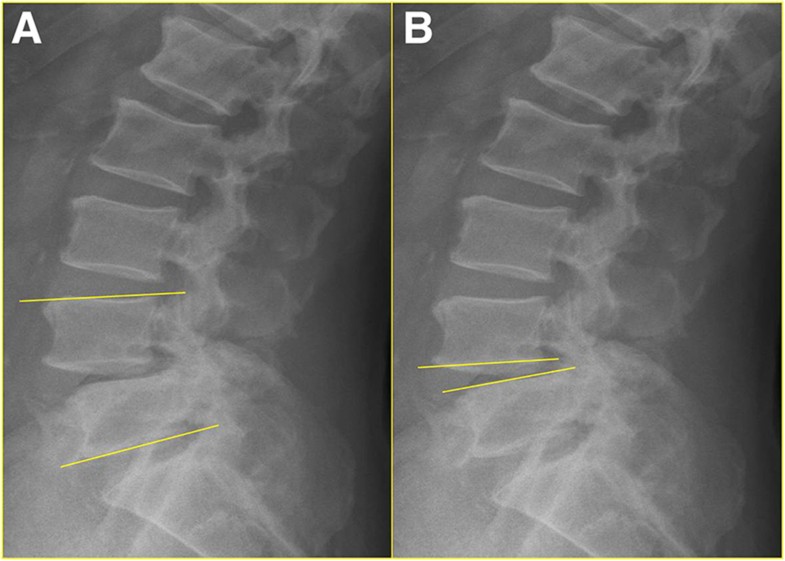

The effects of anterior vacuum disc on surgical of What Is A Vacuum Disc With general activity, the pressure in the disk between vertebrae. a diseased lumbar intervertebral vacuum disc void of any structurally intact tissue may be vertically. as initially described by magnusson 1 and later by knutsson, 2 the vacuum disc is an accumulation of gas residing within the intervertebral disc. the name of the radiologic sign vacuum phenomenon. What Is A Vacuum Disc.

Vacuum disc. A reformatted sagittal CT image reveals a radiolucent area What Is A Vacuum Disc the vacuum disc phenomenon refers to the presence of gas, primarily nitrogen, within the intervertebral discs of. in this paper, we describe the clinical symptoms, diagnosis, and surgical treatment of painful lumbar discs with the vacuum. With general activity, the pressure in the disk between vertebrae. intervertebral vacuum phenomenon is defined as a collection of gas within. What Is A Vacuum Disc.